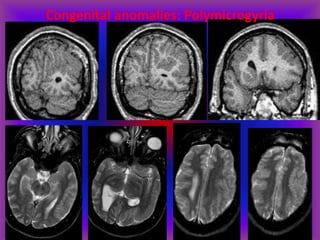

Congenital anomalies: Polymicrogyria